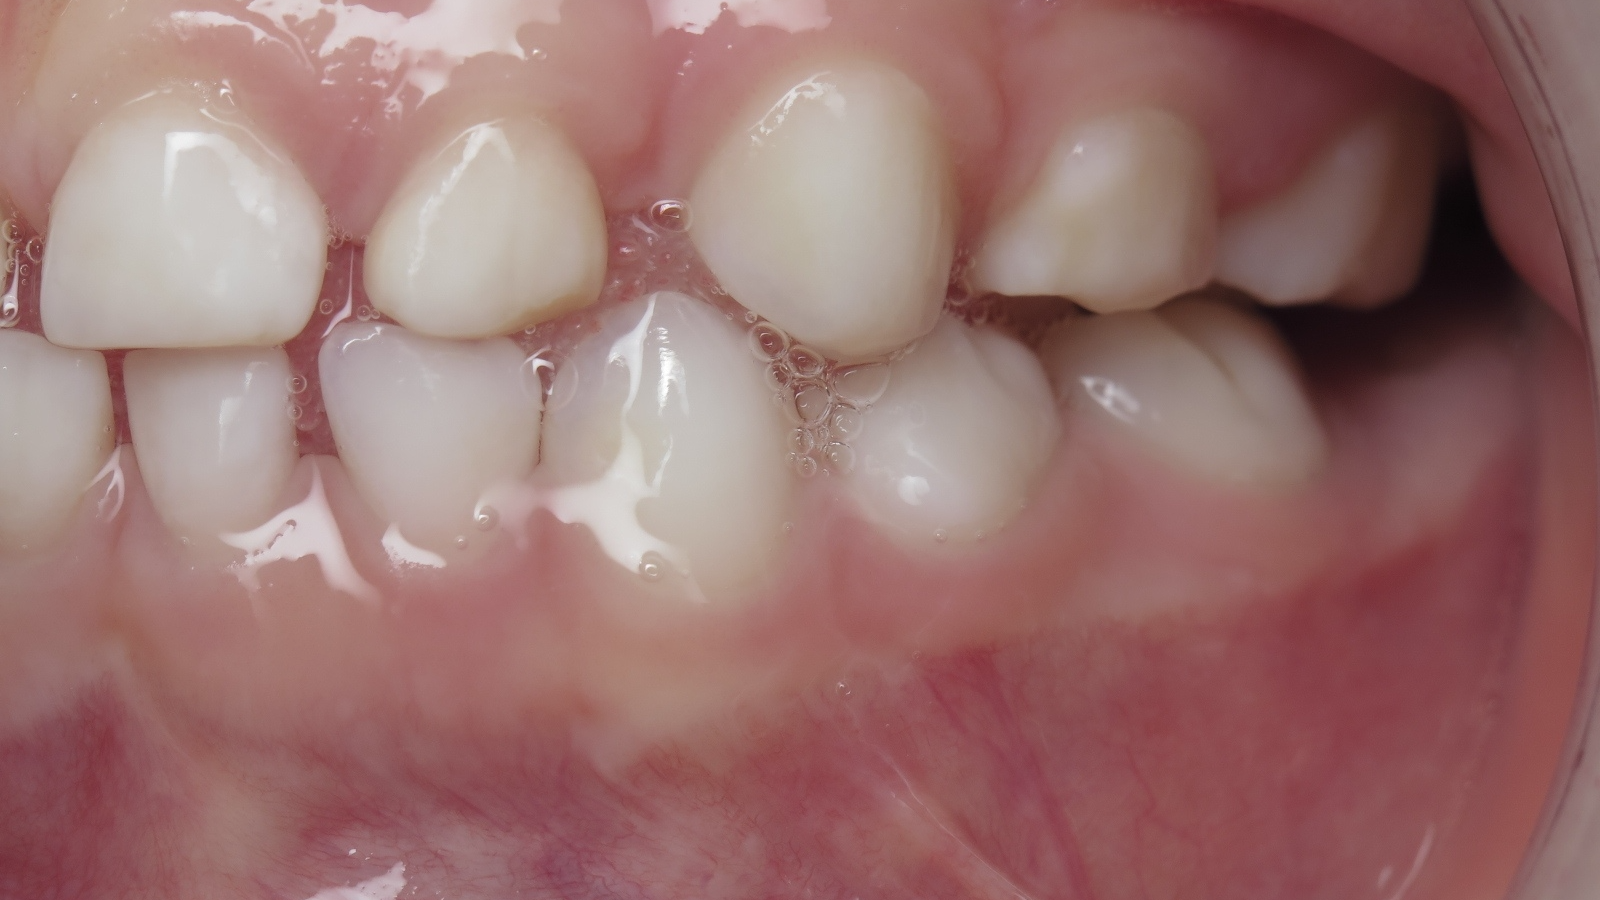

inversion des dents postérieur coté droit